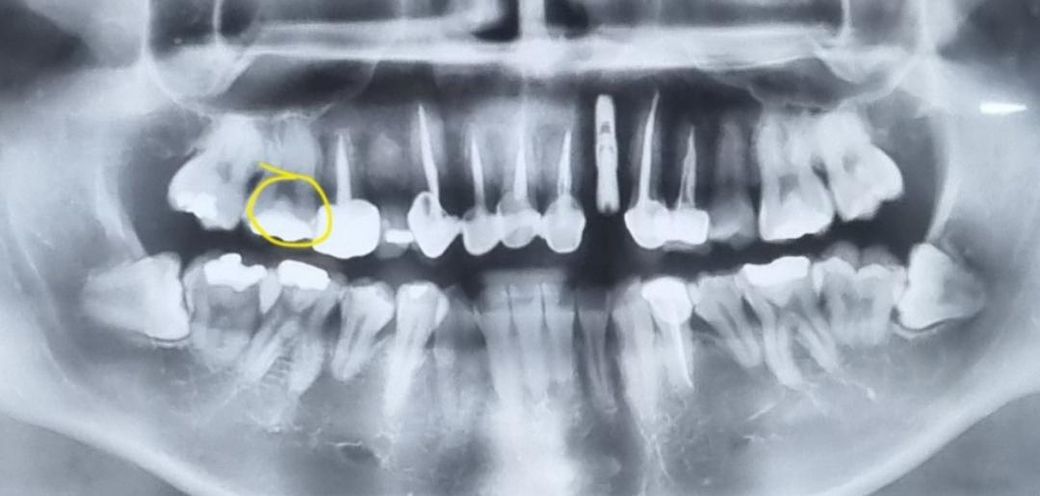

윗 어금니 크라운 어떤걸로 하는게 좋을까요?

저부분이 아말감인데 오래되서 10년이상되었습니다

통증은 없는데 아말감이 사이사이 금가서 치료해야한다고 말씀해주셨습니다

범위가 커서 인레이,레진은 안되고 바로 크라운 해야한다고 말씀하셨는데 자르코니아 vs 크라운 어떤걸 하는게 좋을지 추천 부탁드립니다!

• 1번 째 사진